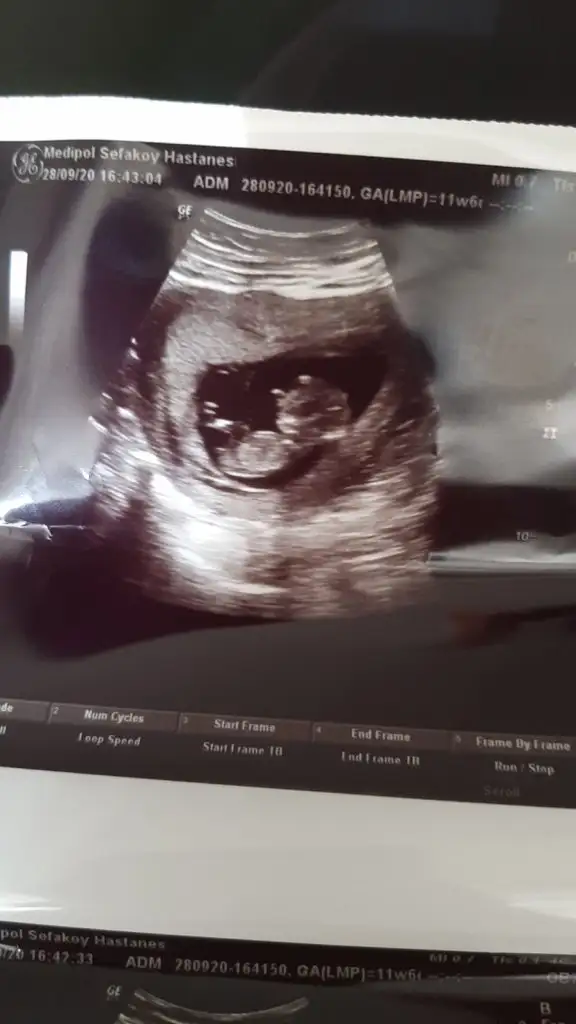

Daha küçükMerhabalar, bu ultrason fotografina gore cinsiyet tahmininiz var midirkalbi 6+4 de 150 atiyordu simdi 9+4 gozuktu bir hafta onden gidiyormus 180 atiyordu. Bir de sag tarafa yerlesmis

Olursa paylaşın 11 12 13 haftalar olur hiç net değil kız dedim ama olmayabilir net değil ilk bebekmi